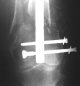

Attached are few examples from our Hospital:

A. Difficult reductions, even in retrograde nailing (my preference, easier control of "small" distal fragment) and it is much, much harder to do it anterograde (Alex, do you have one good case in your collection of anterograde nailing in very distal fractures - as you have suggested that I

Malpositioning is much too common (recurvatum, varus - valgus).

B. Fixation loosening: distal cutting of the nail, non-unions do happen (cases attached).